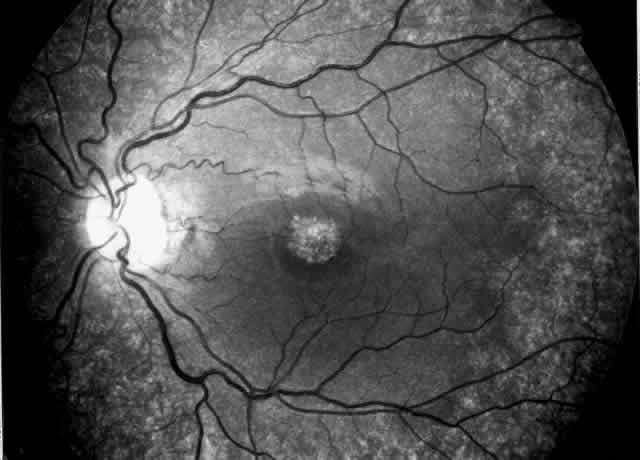

All cystinotic patients have ocular involvement, and older patients with nephropathic cystinosis are at risk of severe ocular complications. In nephropathic cystinosis, crystal deposits usually appear in the cornea within the first year of life. Initially, crystals can be identified in the anterior peripheral part of the cornea by slit lamp biomicroscopy. With time, progressive accumulation of crystals occurs throughout the corneal stroma, inducing photophobia even in young children and provoking a hazy, ground-glass appearance of the cornea in older patients.36 Crystal deposits are also formed in conjunctiva, iris, and retinal pigment epithelium.37 Focal degeneration of the retinal pigment epithelium with patchy depigmentation of the fundus may appear early in life and is generally present by age 7.37 The fundus lesions are bilateral and symmetric and involve mainly the periphery, although some patients also develop atrophic macular changes (Fig. 3). Abnormal retinal function with reduced or extinguished responses on electroretinograms and decreased visual acuity are frequent complications in older cystinotic patients.37,38 Several other complications have been described in patients with nephropathic cystinosis, including superficial punctate keratopathy, recurrent erosions, corneal vascularization, band keratopathy, tight miosis, posterior synechiae, and pupillary-block glaucoma.35,37–39

Fig. 3. Cystinotic fundus changes in a 19-year-old patient, demonstrating a pale optic disc and numerous peripheral and macular small white spots at the level of the retinal pigment epithelium. Fluorescein angiography confirmed marked degenerative changes of the retinal pigment epithelium with macular, peripapillary, and peripheral window defects.